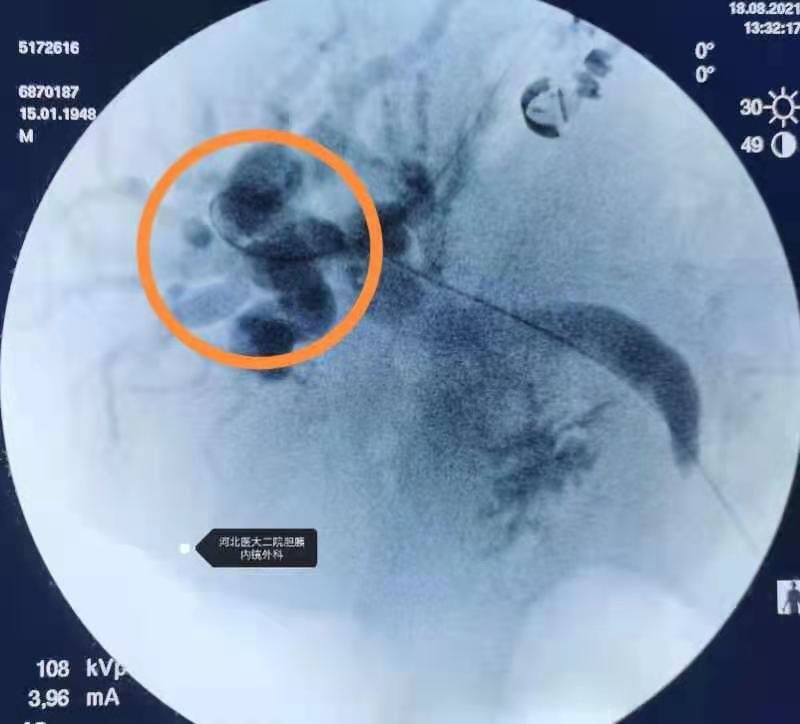

回抽见胆汁后造影。

继续造影。